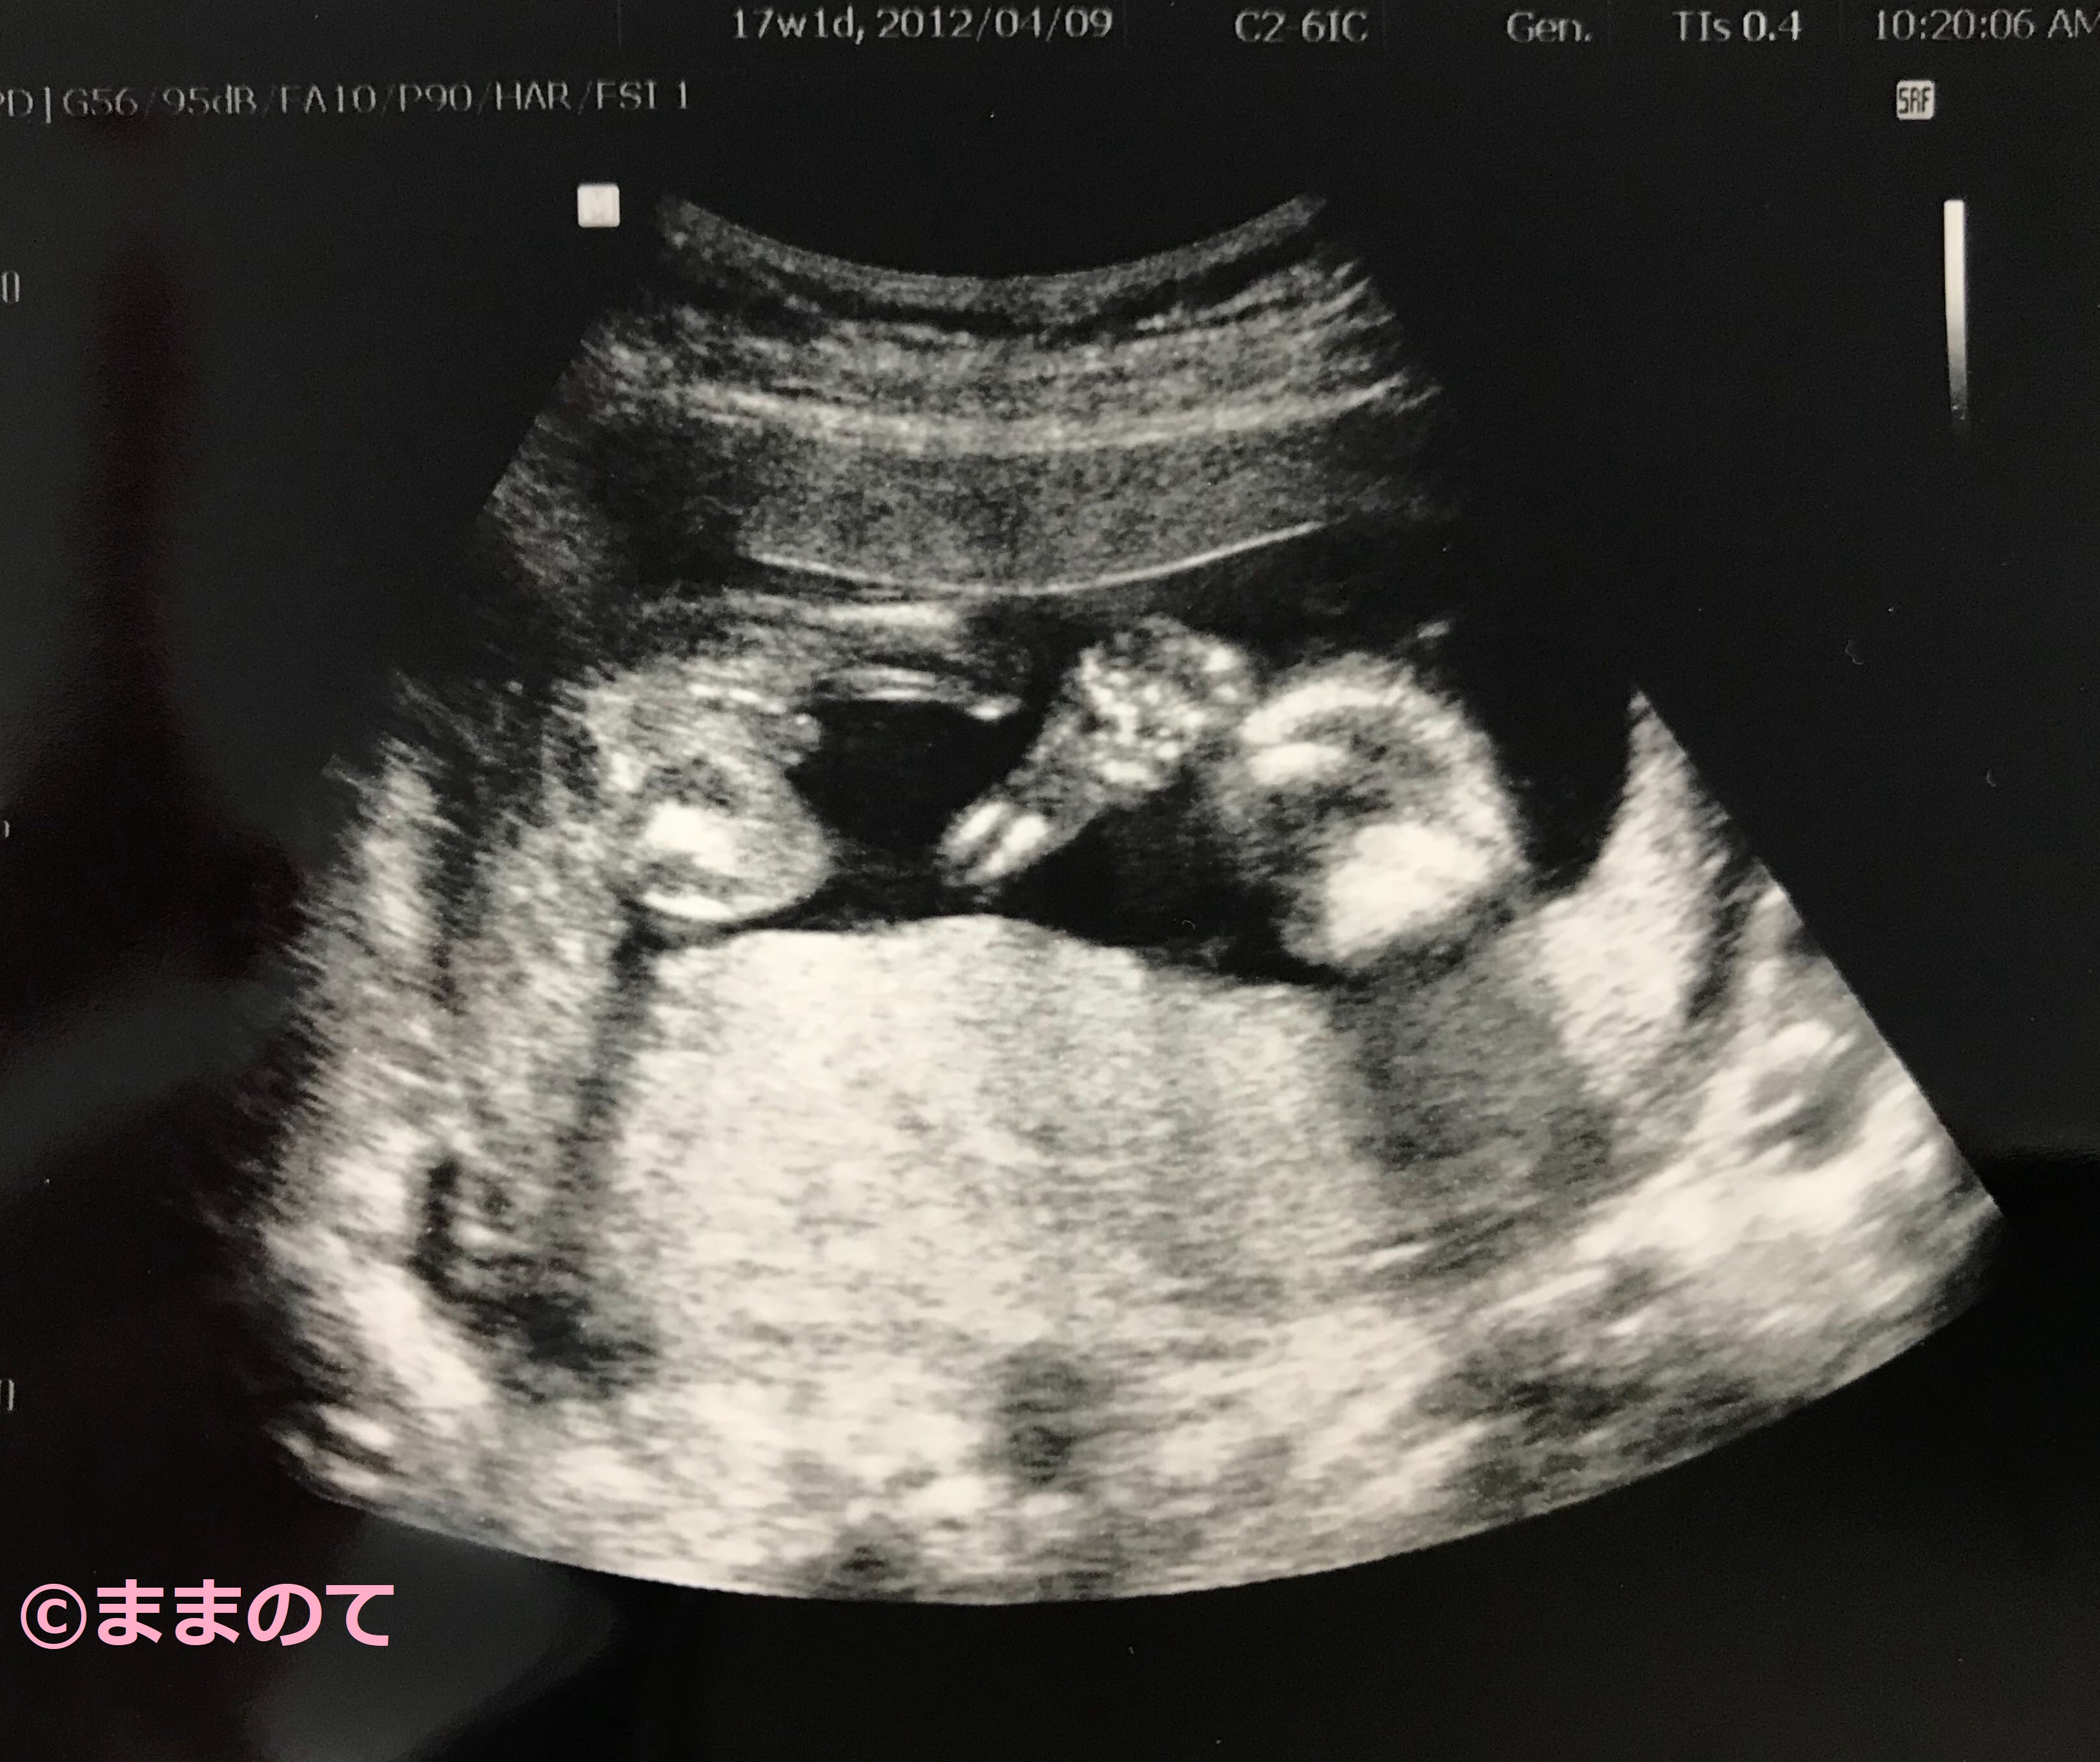

妊娠17週の赤ちゃんのエコー画像

エコーで赤ちゃんがなかなか動かないと心配になるママもいるかもしれません。赤ちゃんの動き方は個性があり、タイミングによってはまったく動きがみられないこともあります。赤ちゃんが寝ている場合もあるので、先生からの指示がなければあまり心配しなくても良いでしょう。